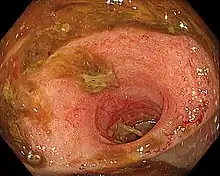

Ileitis caused by capecitabine

Ileítis es la inflamación del íleon, una parte del intestino delgado. La ileítis de Crohn es un tipo de enfermedad de Crohn que afecta el íleon. La ileítis es causada por la bacteria Lawsonia intracellularis.[1] La enfermedad de inflamación humana del intestino no se encuentra asociada con la infección por Lawsonia intracellularis.